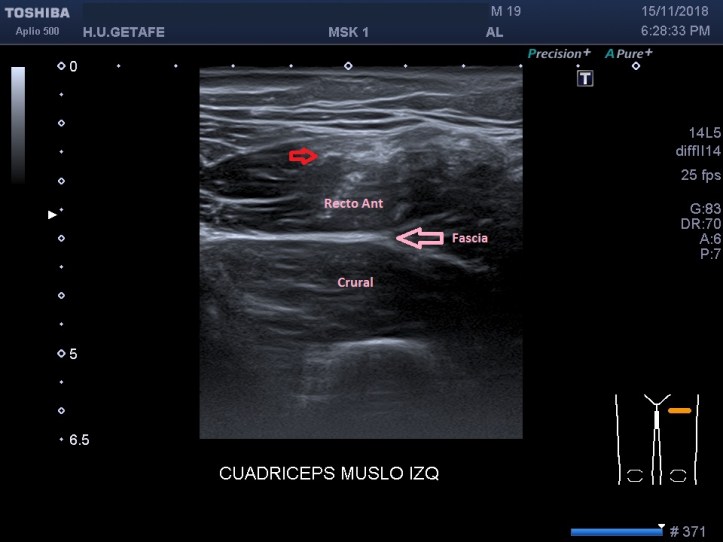

Empiezo la ecografía y compruebo una hendidura en la región afectada descrita anteriormente por el paciente. El lado contralateral parece normal. El Recto anterior izquierdo muestra en la zona «hundida» una imagen hiperecogénica y heterogénea en el teórico lugar del Rafe (flechas rojas), que en la porción más distal de la imagen heterogénea e hiperecogénica anteriormente descrita, es normal.

En este caso, es vital el estudio del tendón intramuscular para seguirlo hasta su origen en la Espina Iliaca Antero-Inferior y ver si está afectado. La lesión corresponde a una rotura de fibras con desinserción parcial del tendón en su origen. Conocer la anatomía, y la localización del Rafe, es imprescindible.

Comparar con el lado contralateral normal en este caso es revelador, en el lado normal vemos un tendón intramuscular normal, en el lado afectado y coincidiendo con la zona de dolor, una imagen alterada de este tendón intramuscular.

I start the ultrasound and check a cleft in the affected region described above. The contralateral side seems normal. The left anterior rectum shows in the «sunken» zone a hyperechogenic and heterogeneous image in the theoretical place of the Rafe, which in the most distal portion of the heterogeneous and hyperechogenic image described above, is normal.

In this case, the study of the intramuscular tendon is vital to follow it to its origin in the Antero-Lower Spine and see if it is affected. The lesion corresponds to a rupture of fibers with partial disintegration of the tendon at its origin. Knowing the anatomy, and the location of the Rafe, is essential.

Comparing with the normal contralateral side in this case is revealing, on the normal side we see a normal intramuscular tendon, on the affected side and coinciding with the area of ​​pain, an altered image of this intramuscular tendon.